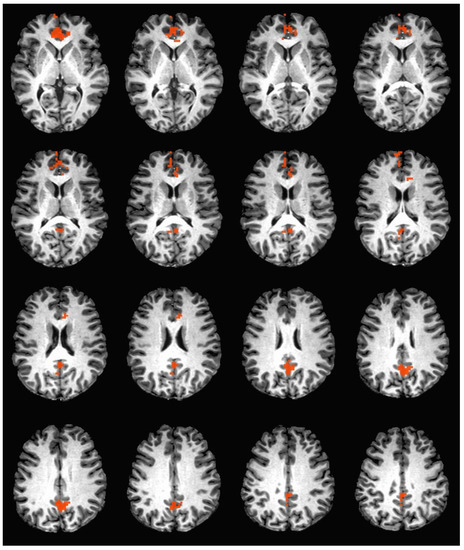

During the hedonic evaluation of caffeine, caffeine non-consumers had significantly greater neuronal activation in the right cuneus, right precuneus, left anterior cingulate, medial frontal gyrus, and left superior frontal gyrus (See Table 4 and Figure 2).

Figure 2. Brain activation during the hedonic evaluation of caffeine. Orange indicates areas where caffeine non-consumers had significantly greater activation in comparison to caffeine consumers.

4.3. Memory Processing Areas

During the hedonic evaluation of caffeine, caffeine non-consumers demonstrated significantly greater activation in right precuneus. During the hedonic evaluation of sucrose, caffeine non-consumers demonstrated significantly greater activation in both the left and right side of the precuneus. The right precuneus has been previously linked to autobiographical memory retrieval [47]. It is of particular interest that this area was activated during the hedonic evaluation of caffeine, an experience that would not be common in caffeine non-consumers. The precuneus is an area previously associated with episodic memory retrieval, the ability to recall a previously experienced stimulus [48]. Continuous theta burst stimulation (cTBS) over the precuneus in a picture memory task was associated with a decrease in source memory errors and improvement in context retrieval, suggesting that the precuneus is integral to a memory encoding and retrieval network [48]. During a source and item-recognition memory task, the left precuneus was activated during memory retrieval [49].

During the hedonic evaluation of caffeine and sucrose, activation in the anterior cingulate cortex (ACC) was significantly greater in caffeine non-consumers. During the hedonic evaluation of caffeine, only activation in the left anterior cingulate cortex was found to be significantly greater in caffeine non-consumers in comparison to caffeine consumers. Lateralization in the ACC has been found during error processing and conflict monitoring, where correct inhibitions only occurred in the right ACC [42]. Further, observational fear learning has been found to only be activated in the right, but not the left ACC [43]. The distinction that right ACC activation only occurred during the hedonic evaluation of sucrose and not during the hedonic evaluation of caffeine suggests that sucrose may have been a more intense experience for caffeine non-consumers. Psychophysical data supports this assertion, as caffeine non-consumers provided significantly higher intensity ratings for sucrose post-scan when compared to caffeine consumers (Table 3).

4.4. Information Processing

Activation in information processing pathways was observed during hedonic evaluation of all three tastants. Activation in the right superior frontal gyrus (SFG) was significantly higher during the hedonic evaluation of sucrose. The right SFG has been linked to functioning in cognitive control, such that greater activation was linked to more efficient response inhibition, less motor urgency, as well as greater self-regulation [52,53]. The left SFG was significantly higher during the hedonic evaluation of caffeine in caffeine non-consumers. The superior frontal gyrus, particularly the left SFG, has been associated with performing higher cognitive functions associated with working memory retrieval, especially in relation to task-related behavioral goals [54].